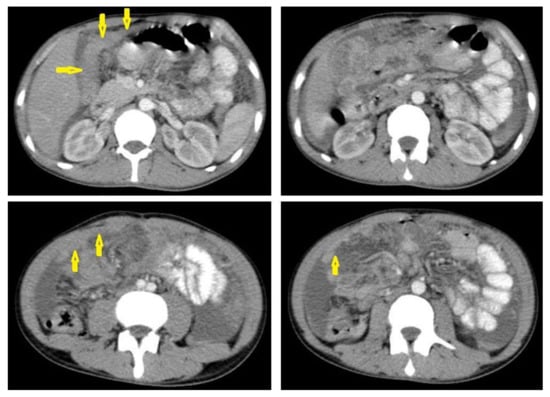

• Tuberculous lymphadenitis (Figure 20) is one of the most common radiological manifestation of abdominal TB which frequently involves multiple groups such as mesenteric and upper paraortic LNs. The majority of patients have enlarged lymph nodes with a low-attenuation center and peripheral-enhancing rim, which is characteristic of TB [45,46]. LNs may show peripheral rim enhancement, inhomogeneous, homogeneous, or no enhancement after contrast administration. Other patterns of LNs include conglomerate LNs with areas of necrosis, more than three enlarged or normal homogenous LNs in one section, or calcified LNs [45]. TB can mimic several other conditions, such as lymphoma, amebiasis, Crohn’s disease, and adenocarcinoma [47].

Figure 20. Tuberculous lymphadenitis in a 27-year-old women with cachexia, loss of appetite and cough. Axial abdominal CT image shows enlarged mesenteric, periaortic, and portahepatis lymph nodes (LNs), (short arrows) due to TB, which usually involves multiple groups, such as mesenteric and upper paraortic LNs. The image also shows relatively dense ascites and remarkable omental thickening forming cake-like mass (long arrow).